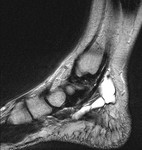

[画像診断]足根管症候群、足根洞症候群、MRI所見について 2011-04-14

・足根管;足関節内側、内果後面・踵骨・屈筋支帯・母趾外転筋に挟まれる。

・足根管症候群;後脛骨神経の絞扼による足の痺れや知覚異常、原因は炎症、腫瘍、外傷

・足根洞;距骨溝と踵骨溝の凹部にできた空間、足部外側へ開口

・足根洞症候群;内部の脂肪組織や滑膜の炎症、骨間距踵靭帯の損傷で発生

・足根管症候群も足根洞症候群も、大部分の原因は外傷

<MRI>

足根管症候群;後脛骨神経を絞扼する原因疾患の同定、特に腫瘍

・ガングリオンのような腫瘍性病変は外傷歴のない足根管症候群の原因として高頻度。

・載距突起過形成

足根洞症候群;足根洞内の脂肪組織変性・炎症、骨間距踵靭帯損傷の評価

<鑑別診断>

・距踵関節癒合症

・後脛骨筋腱機能不全症

・第5中足骨近位骨端の剥離骨折(ゲタ骨折)

参考;勘ドコロ P169

症例は、ガングリオンによる足根管症候群の一例。